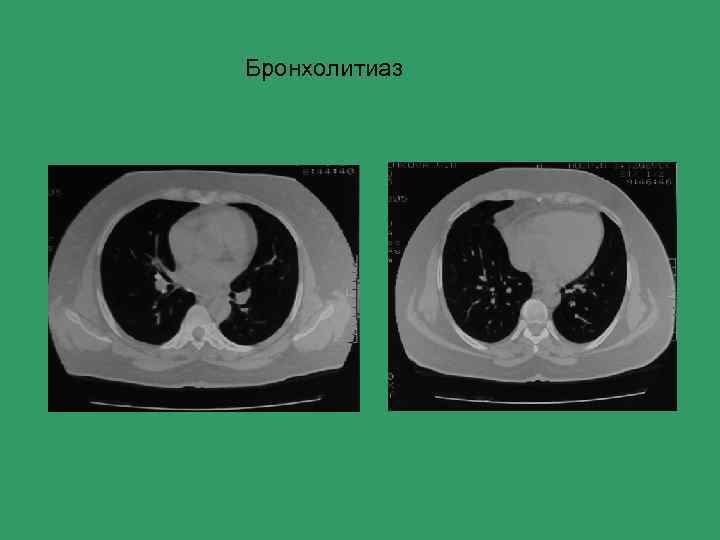

Бронхолитиаз